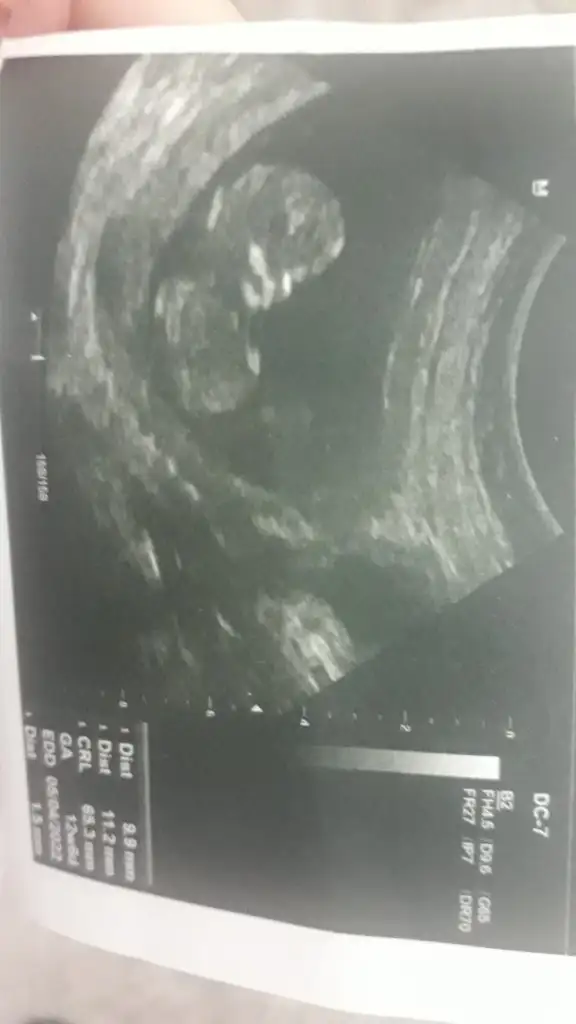

Banada tahmin yapabilir misiniz 12 haftalık

20210929_115839-jpg.2924970

ttecrübeli bayanlar yorum yaparsaniz cok sevinirim...

20210929_115824.webp

• 20210929_115809.webp

20210929_115809.webp

18,3 KB · Görüntüleme: 95